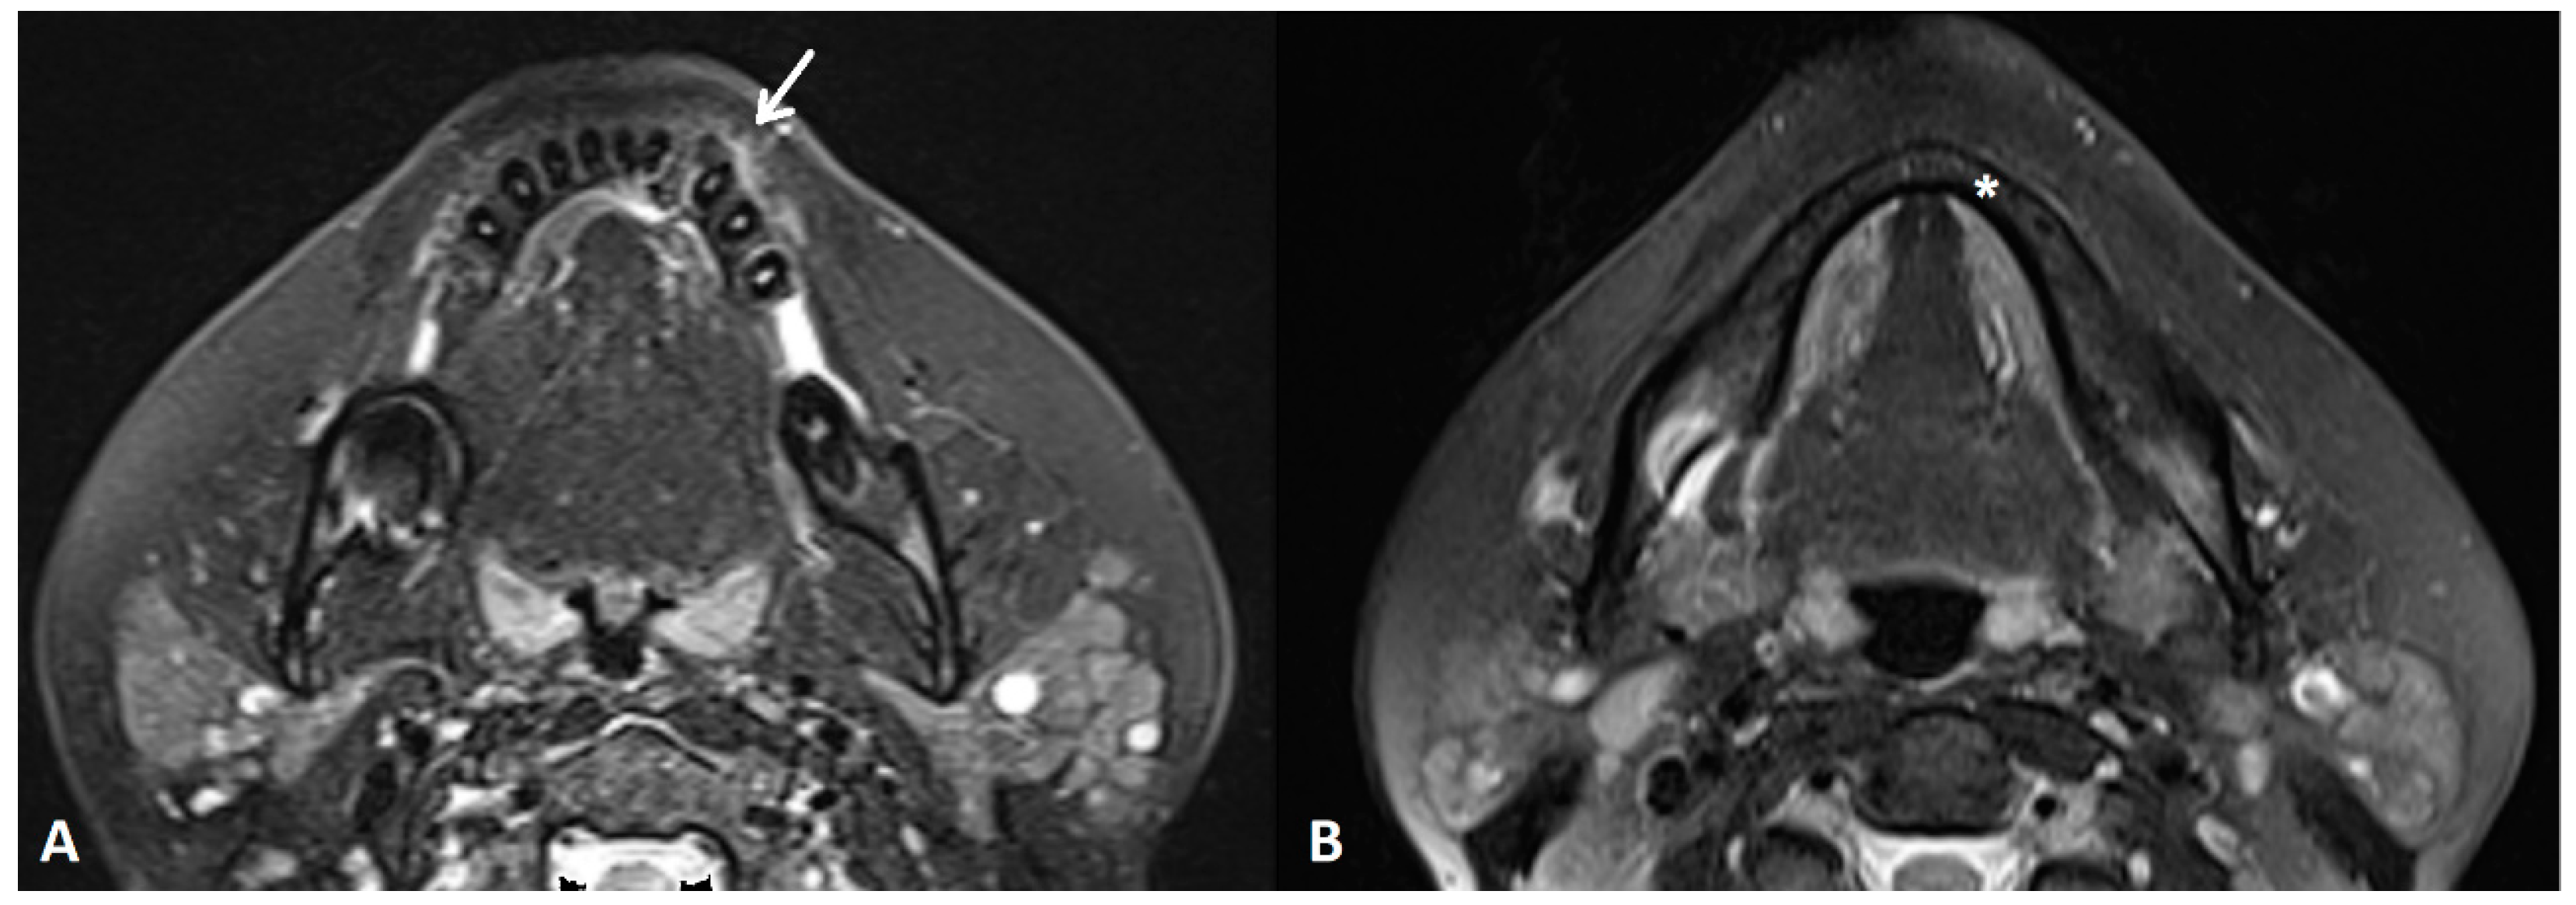

Figure 3. An MRI T2W FS sequence demonstrated a bone lesion in the reported area with irregular focuses of the chondroid/osteoid matrix with non-homogenous signal intensity and a visible periosteal reaction (white arrow) (A). There was no alteration of the bone marrow signal intensity in the mandible (asterisk) (B). The patient underwent left marginal resection of the mandible, extending from the region of the first molar posteriorly to the medial aspect of the right lower lateral incisor medially. Postoperative histopathology diagnosed the tumor as conventional CS, grade II, with positive resection margins. Therefore, the multidisciplinary team (MDT) suggested oncological follow-up every three months, at least for the first year.